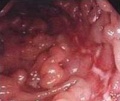

克罗恩病